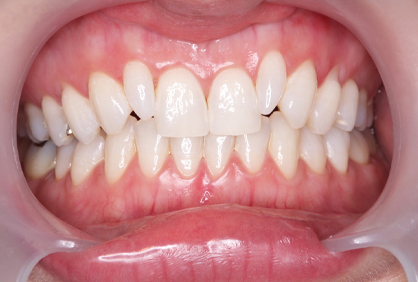

初診時

初診時、前歯の角度はかなり前に向かって生えています。この状態から神経の治療を行うことなく、かぶせ物で角度を変えるのは、限界があるとお伝えして、神経の治療をまず行なってから、歯を削って仮歯を入れる治療計画を伝えて行なった。

セラミックセット時

初めに仮歯に置き換えてから問題なければ、仮歯を最終的な形のプロビに置き換えます。プロビにて歯肉とのマッチングや形や出具合を確認してもらい約1ヶ月の期間使用してもらいます。問題がなければ、最終的な型採りを行い、セラミックの試適、そして完成となりました。